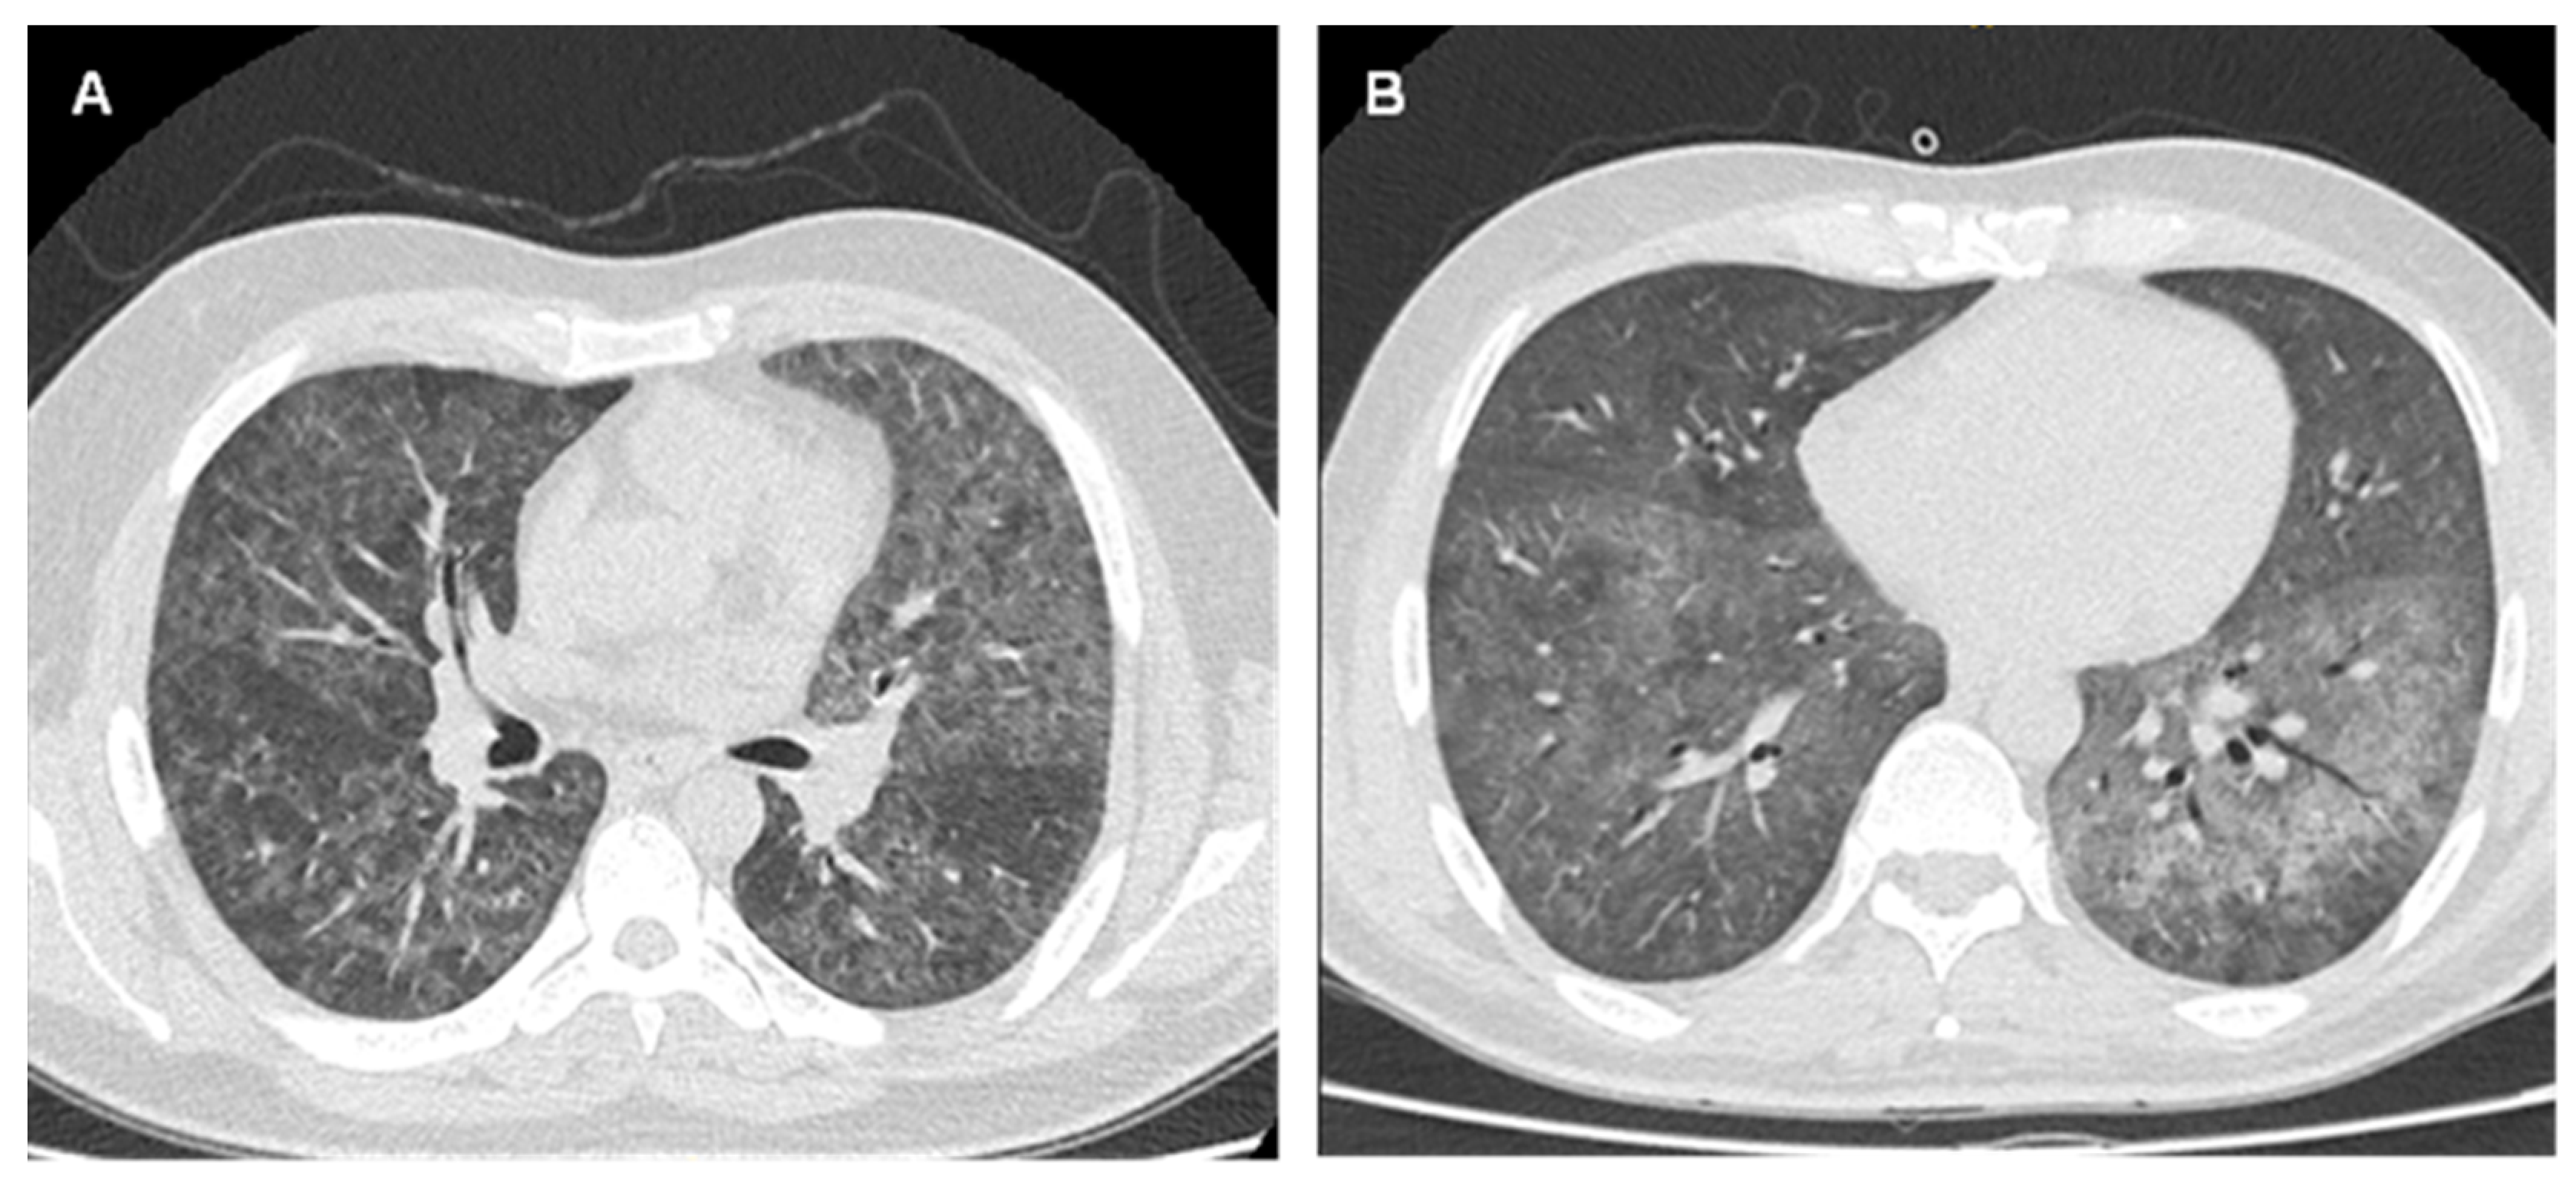

| 1 (CEMT21) | 40/M | BAL | 1 | New diagnosis | 206 | CT with GGO. | No | Hospitalization (Medicine) | SMX-TMP 800/160, 1 tablet every 8 h orally for 7 days. Due to renal failure, change to PQ 15 mg/day + CLDM 600 1 tablet every 8 h. Total duration 21 days | Survived |

| 2 (CEMT20) | 34/M | Sputum | 1 and 2 | 8 years | 31 | Cough with expectoration, dyspnea. CT with bilateral GGO. | W.I | Hospitalization (Medicine) | SMX-TMP 800/160, 2 tablets every 8 h orally. Due to severe ADR, switch to PQ 30 mg/day + CLDM 600 mg 1 tablet every 8 h. Total duration 21 days. | Survived |

| 3 (CEMT16) | 45/M | Sputum | 4 | New diagnosis | 10 | Progressive irritating cough, dyspnea, feeling feverish. CT with bilateral GGO. | Yes | Hospitalization (CPU) | SMX-TMP 400/80, 3 vials every 12 h IV, associated with CAS and CLDM due to clinical deterioration. Total duration 21 days | † |

| 4 (CEMT15) | 30/M | Sputum | 3 | 11 years | 4 | Dry cough, exertional dyspnea for 1 month, night sweats. CT with interstitial infiltrate and bilateral GGO | No | Hospitalization (Medicine) | SMX-TMP 400/80, 4 vials every 8 h IV. Total duration 21 days | Survived |

| 6 (CEMT22) | 23/M | BAL | 3 | 5 months | 21 | Cough, dyspnea, night fever. CT with condensing image, scarce GGO. | No | Hospitalization (Medicine) | SMX-TMP 400/80, 4 vials every 8 h IV for 11 days. Change to PQ 30 mg/day + CLDM 600 mg, 1 tablet every 8 h. Total duration 21 days. | Survived |

| 7 (CEMT2) | 57/M | Sputum | 3 | 11 years | 38 | Cough with expectoration, dyspnea, feeling feverish. CT with bilateral GGO, mostly in the left lung | No | Ambulatory | SMX-TMP 800/160, 2 tablets every 8 h orally. Total duration 21 days. | Survived |

| 9 (CEMT5) | 49/M | BAL | 2 | 1 month | 29 | Cough with expectoration, dyspnea, and fever | No | Hospitalization (CPU) | SMX-TMP 15 mg/kg/day IV for 18 days and then 3 days orally at the same dose. Hydrocortisone 100 mg IV every 8 h for 5 days, then 50 mg every 8 h for 5 days, and then prednisone 20 mg/day orally. | Survived |

| 10 (CEMT99) | 41/M | Sputum | 2 | New diagnosis | 45 | Cough, tachypnoea, CT with ground glass infiltrate | No | Hospitalization (CPU) | SMX-TMP 800/160 in doses of 17 mg/kg in 3 doses (of the TMP component). Total duration 21 days. | Survived |

| 11 (CEMT98) | 28/M | BAL | 2 | New diagnosis | 9 | Pneumonia with cough, dyspnea, fever, and night sweats. Chest X-ray shows multiple solid nodules of random and perilymphatic distribution | No | Hospitalization (Medicine) | SMX-TMP 800/160, 2 tablets every 8 h orally to complete 17 mg/kg of TMP. Total duration 21 days | Survived |

| 12 (CEMT97) | 46/F | BAL | 3 | 12 years | 54 | Multifocal pneumonia, respiratory failure. CT chest with bilateral GGO | No | Hospitalization (CPU) | SMX-TMP 400/80, 3 vials every 6 h IV. ANI was associated. Due to clinical deterioration, CAS and CLDM were added. Total duration 21 days. | Survived |

| 13 (CEMT90) | 43/M | Sputum | 1 | 2 years | 12 | Cough, dyspnea, sore throat, diaphoresis, and desaturation. CT shows diffuse bilateral GGO | No | Hospitalization (Medicine) | SMX-TMP 400/80, 3 vials every 8 h IV for 12 days. Then 800/160 2 tablets every 8 h orally. Due to toxicity, pancytopenia, and transaminase elevation, change to PQ 15 mg/day + CLDM 600 mg 1 tablet every 8 h. Total duration 21 days. | Survived |

| 14 (CEMT85) | 49/M | Sputum | 4 | New diagnosis | W.I | Cough with expectoration, dyspnea at rest, feeling feverish. Chest CT reveals extensive areas with bilateral GGO | No | Hospitalization (Medicine) | SMX-TMP 400/80, IV and then 800/160 2 tablets every 8 h orally. Total duration 21 days. | Survived |

| 15 (CEMT94) | 55/M | Pharyngeal lavage | 1 | 4 years | 52 | Dry cough, dyspnea, tiredness, loss of appetite. Chest X-ray with interstitial infiltrates | Yes | Ambulatory | SMX-TMP 800/160: 2-2-1 (tablets) every 8 h orally. Total duration 21 days. | Survived |